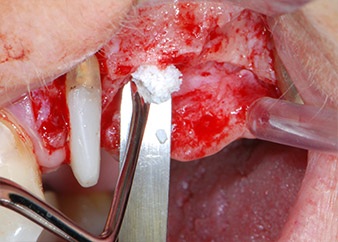

Въпреки това, ние се придържахме към първоначалния си план да запазим и двата зъба като абатмънти за временен мост по време на 6-месечната остеоинтеграция на имплантите. При повторна интервенция, ситуацията трябва да се преразгледа. Първо, в опит да се овладее ендо-перио проблема, останалата повърхност на зъба е внимателно обработена с пиезохирургично оборудване (Piezomed, W&H, използван с накрайник S1 под формата на шпатула, първоначално проектиран за ерозия на латералната синусна стена) (Фиг. 4).

След това апексът се изпилява със същия инструмент, за да се отстрани остатъчната инфектирана апикална тъкан и да се намали възможното допълнително усложнение по кореновите канали (апикоектомия) (Фиг. 5). Ретроградно запълване не е необходимо, защото ортоградното запълване току-що е ревизиран.